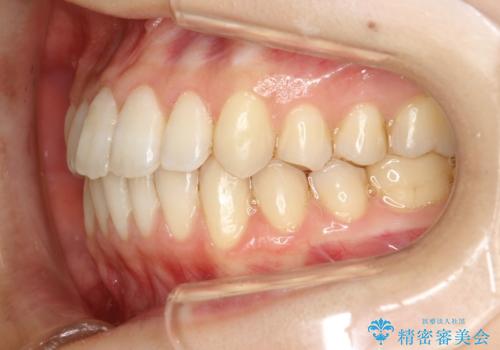

前歯のガタガタをインビザラインで目立たず矯正

- 目立たずに前歯を矯正したいとのことで来院されました。

歯と歯の間にわずかに隙間を作りスペースを確保し、インビザラインにて矯正を行うこととなりました。

前歯の微調整に少し時間がかかりましたが、整った歯並びにすることができました。